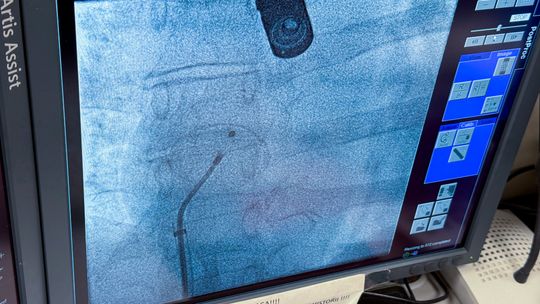

Historyczny zabieg w garwolińskim szpitalu. Po raz pierwszy zamknięto ASD bez operacji